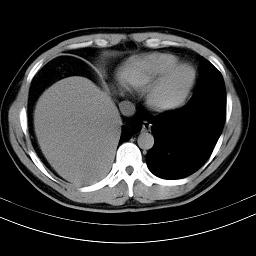

标题: CT18388:肝脏膈肌间隙内大量脂肪密度影 [打印本页]

标题: CT18388:肝脏膈肌间隙内大量脂肪密度影

是脂肪不是气体,有时候会碰到这样的病人,脂肪过多吧。

腹腔脂肪沉积过多

膈下脂肪沉积。

考虑膈下脂肪沉积。

激素治疗的病人容易脂肪沉积